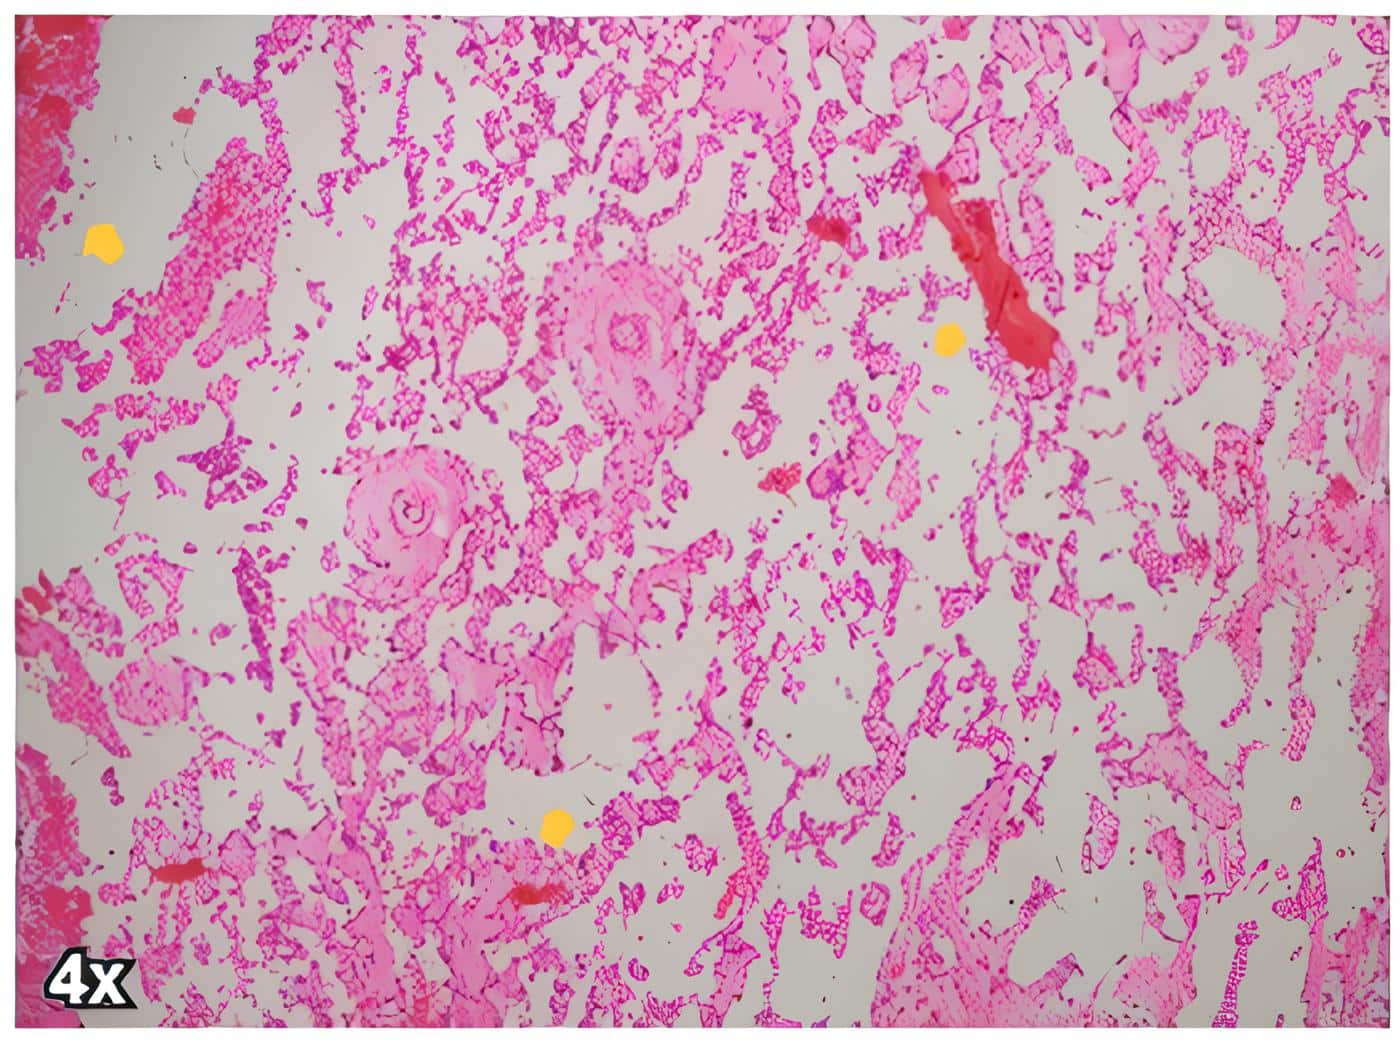

En el control a los 20 días del procedimiento quirúrgico, se entregó reporte de patología donde se confirmaba el diagnostico oncológico de angiosarcoma de mama de bajo grado, ya que en los cortes de hematoxilina y eosina se identificó una lesión tumoral constituida por canales vasculares anastomosados, extravasación de eritrocitos estromales y células endoteliales con hipercromasia nuclear leve (Figuras 1 y 2), con positividad para los marcadores de inmunohistoquimica CD34 y ERG (Figura 3).

Figura 1. Corte del angiosarcoma de mama de la paciente, donde se aprecian los canales vasculares anastomosados (flechas amarilla). Tincion de hematoxilina y eosina 4x. Fuente: Todas las imágenes proceden de la base de datos de las placas histológicas localizadas en el área de patología del Hospital Universitario San Ignacio.